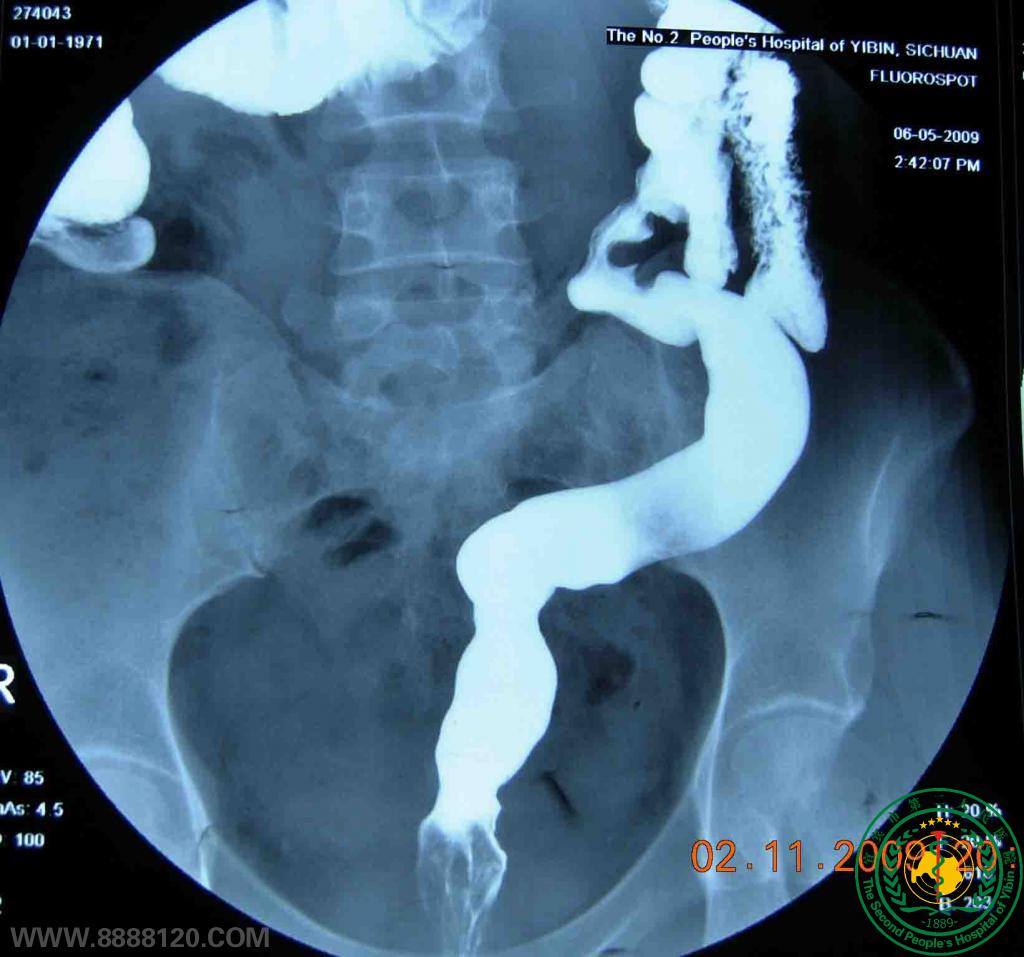

胃肠疝外科近日成功腹腔镜下治疗降结肠重复畸形1例

胃肠疝外科近日成功腹腔镜下治疗降结肠重复畸形1例1141

宜宾市第二人民医院 图文